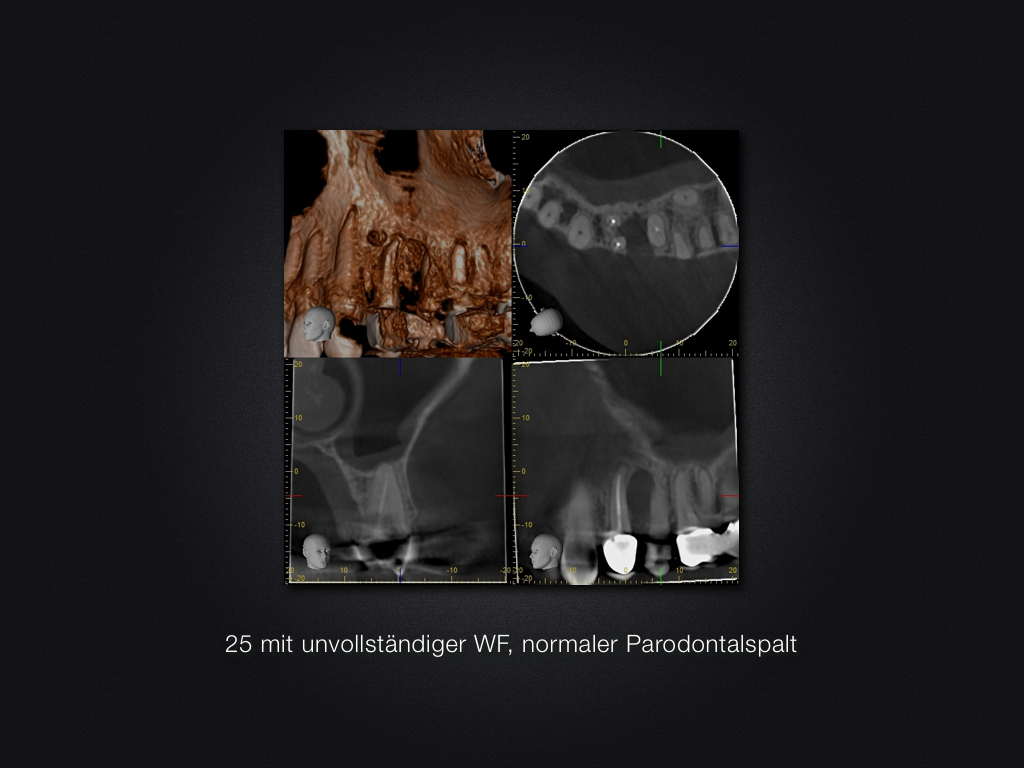

Ohne Erfolg …